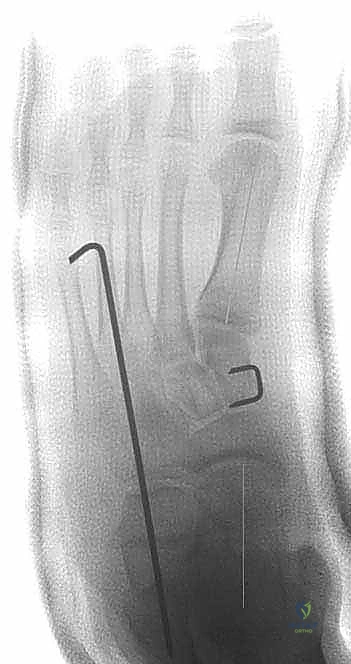

5. التثبيت الداخلي (Internal Fixation)

لضمان عدم تحرك الطعم العظمي أثناء فترة الالتئام، يتم تثبيت التكوين الجديد. يستخدم الدكتور هطيف أحدث تقنيات التثبيت، والتي قد تشمل شريحة معدنية صغيرة مع مسامير (Plate and Screws)، أو مسامير معدنية تمر عبر العظم، أو أسلاك كيرشنر (K-wires)، وذلك لضمان أقصى درجات الثبات الميكانيكي.

يتم التأكد من صحة التثبيت والتصحيح باستخدام جهاز الأشعة السينية المباشر (C-arm Fluoroscopy) داخل غرفة العمليات قبل إغلاق الجرح.